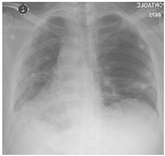

Furthermore, some of the examples of the COVID-19 positive and the healthy patients from the dataset are included in Table 5. The clinical data represent the attributes sequence, i.e., gender, age, body temperature, pulse rate, respiratory rate, blood pressure systolic, blood pressure diastolic, shortness of breath, cough, other symptoms, diabetes mellitus, hypertension, cardiac disease, dyslipoproteinemia, chronic kidney disease, and other chronic diseases.

Table 5.

Sample CXR and clinical data for the COVID-19 positive and healthy cases.